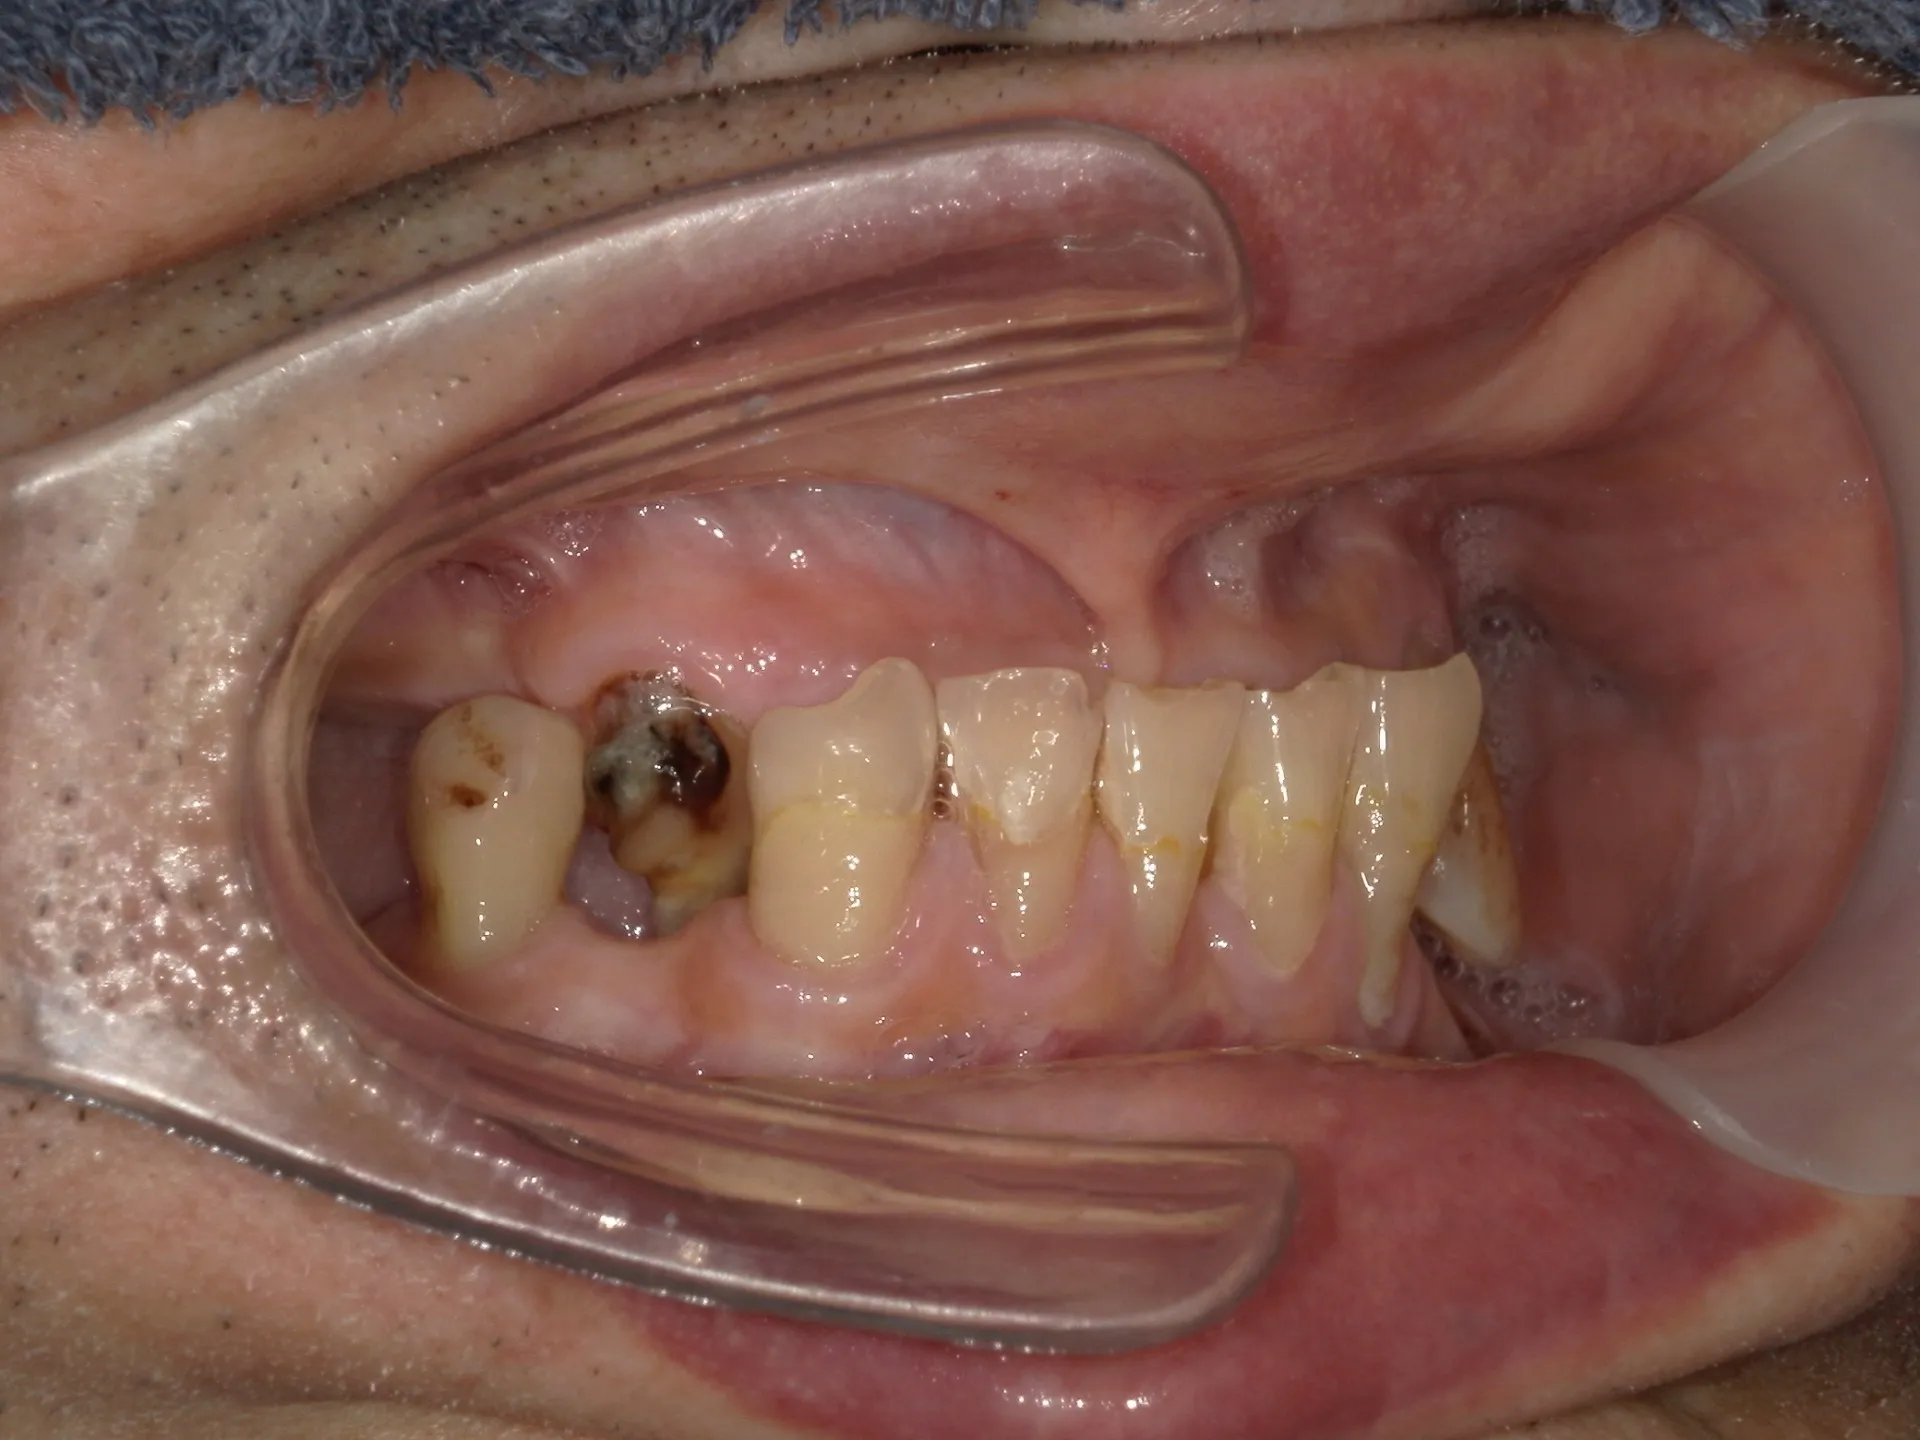

上記の写真は上下に歯があるものの噛むと歯が歯茎に当たるまで深く嚙み込んで入違った歯がすれ違って噛んでいることが分かります。

すれ違い咬合は上下の歯があるものの上下の歯が全く接触できないように歯が抜けてしまっているために無歯顎とほぼ同じように普通以上に噛み込んでしまい、歯が歯茎にぶつかるまで噛めてしまいます。